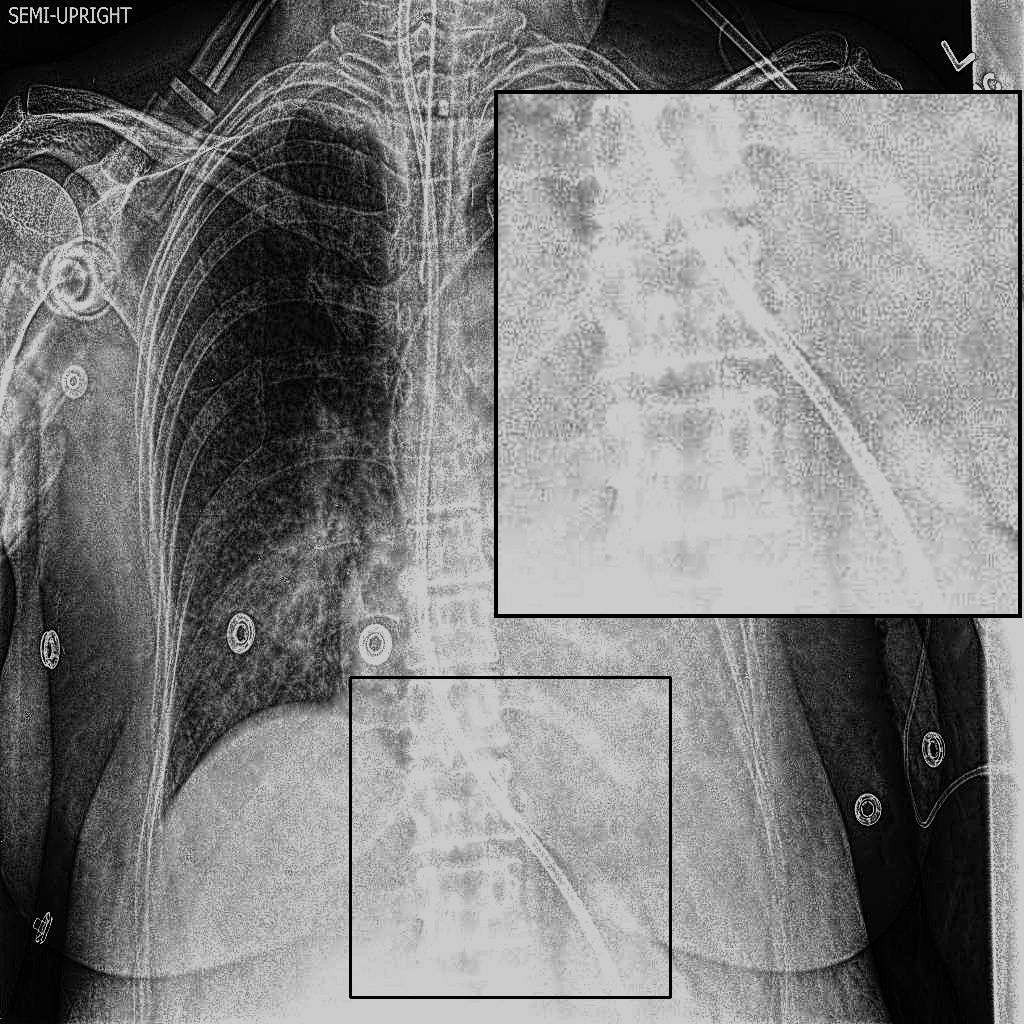

Figure 4: Visual examples of different image enhancement methods across datasets; first and second columns present results from the JSRT and Montgomery County Chest X-ray datasets, respectively, while third and fourth columns show results from the NIH Chest X-ray and CheXpert datasets

4.5 A Visual Assessment

Fig. 4 presents representative visual examples demonstrating the superiority of our method in enhancing vertebral contrast compared to several traditional and learning-based image enhancement techniques. The first and second columns show results from the JSRT and Montgomery County Chest X-ray datasets, while the third and fourth columns display results from the NIH ChestX-ray14 and CheXpert datasets. Across all datasets, the highlighted regions of interest (ROIs) emphasize the spinal areas, where fine structures and subtle details are critical for diagnostic assessment. Our method, XVertNet, consistently reveals clearer and more distinct spinal structures without introducing notable artifacts, preserving both global and local anatomical information. In contrast, traditional methods such as CLAHE [7] and Farbman et al. [19] often fail to enhance these subtle features effectively, either producing over-smoothed results or excessively sharpening noise. Similarly, learning-based methods such as ZSSR [43] and Madmad et al. [68] exhibit difficulties in generalizing across different datasets, leading to either insufficient enhancement or visible artifacts. Zero-DCE [33], although effective for natural images, struggles to adapt to the uniform and low-contrast nature of medical X-rays and was not able to supply clear enough contrast-enhanced vertebral structures.

These visual comparisons underline the clinical relevance of our approach. XVertNet successfully enhances diagnostically important structures, particularly in challenging anatomical regions like the spine, where competing methods either distort the features or fail to sufficiently reveal them. This highlights the value of integrating targeted enhancement strategies that are specifically tailored to the unique characteristics of medical imaging data.